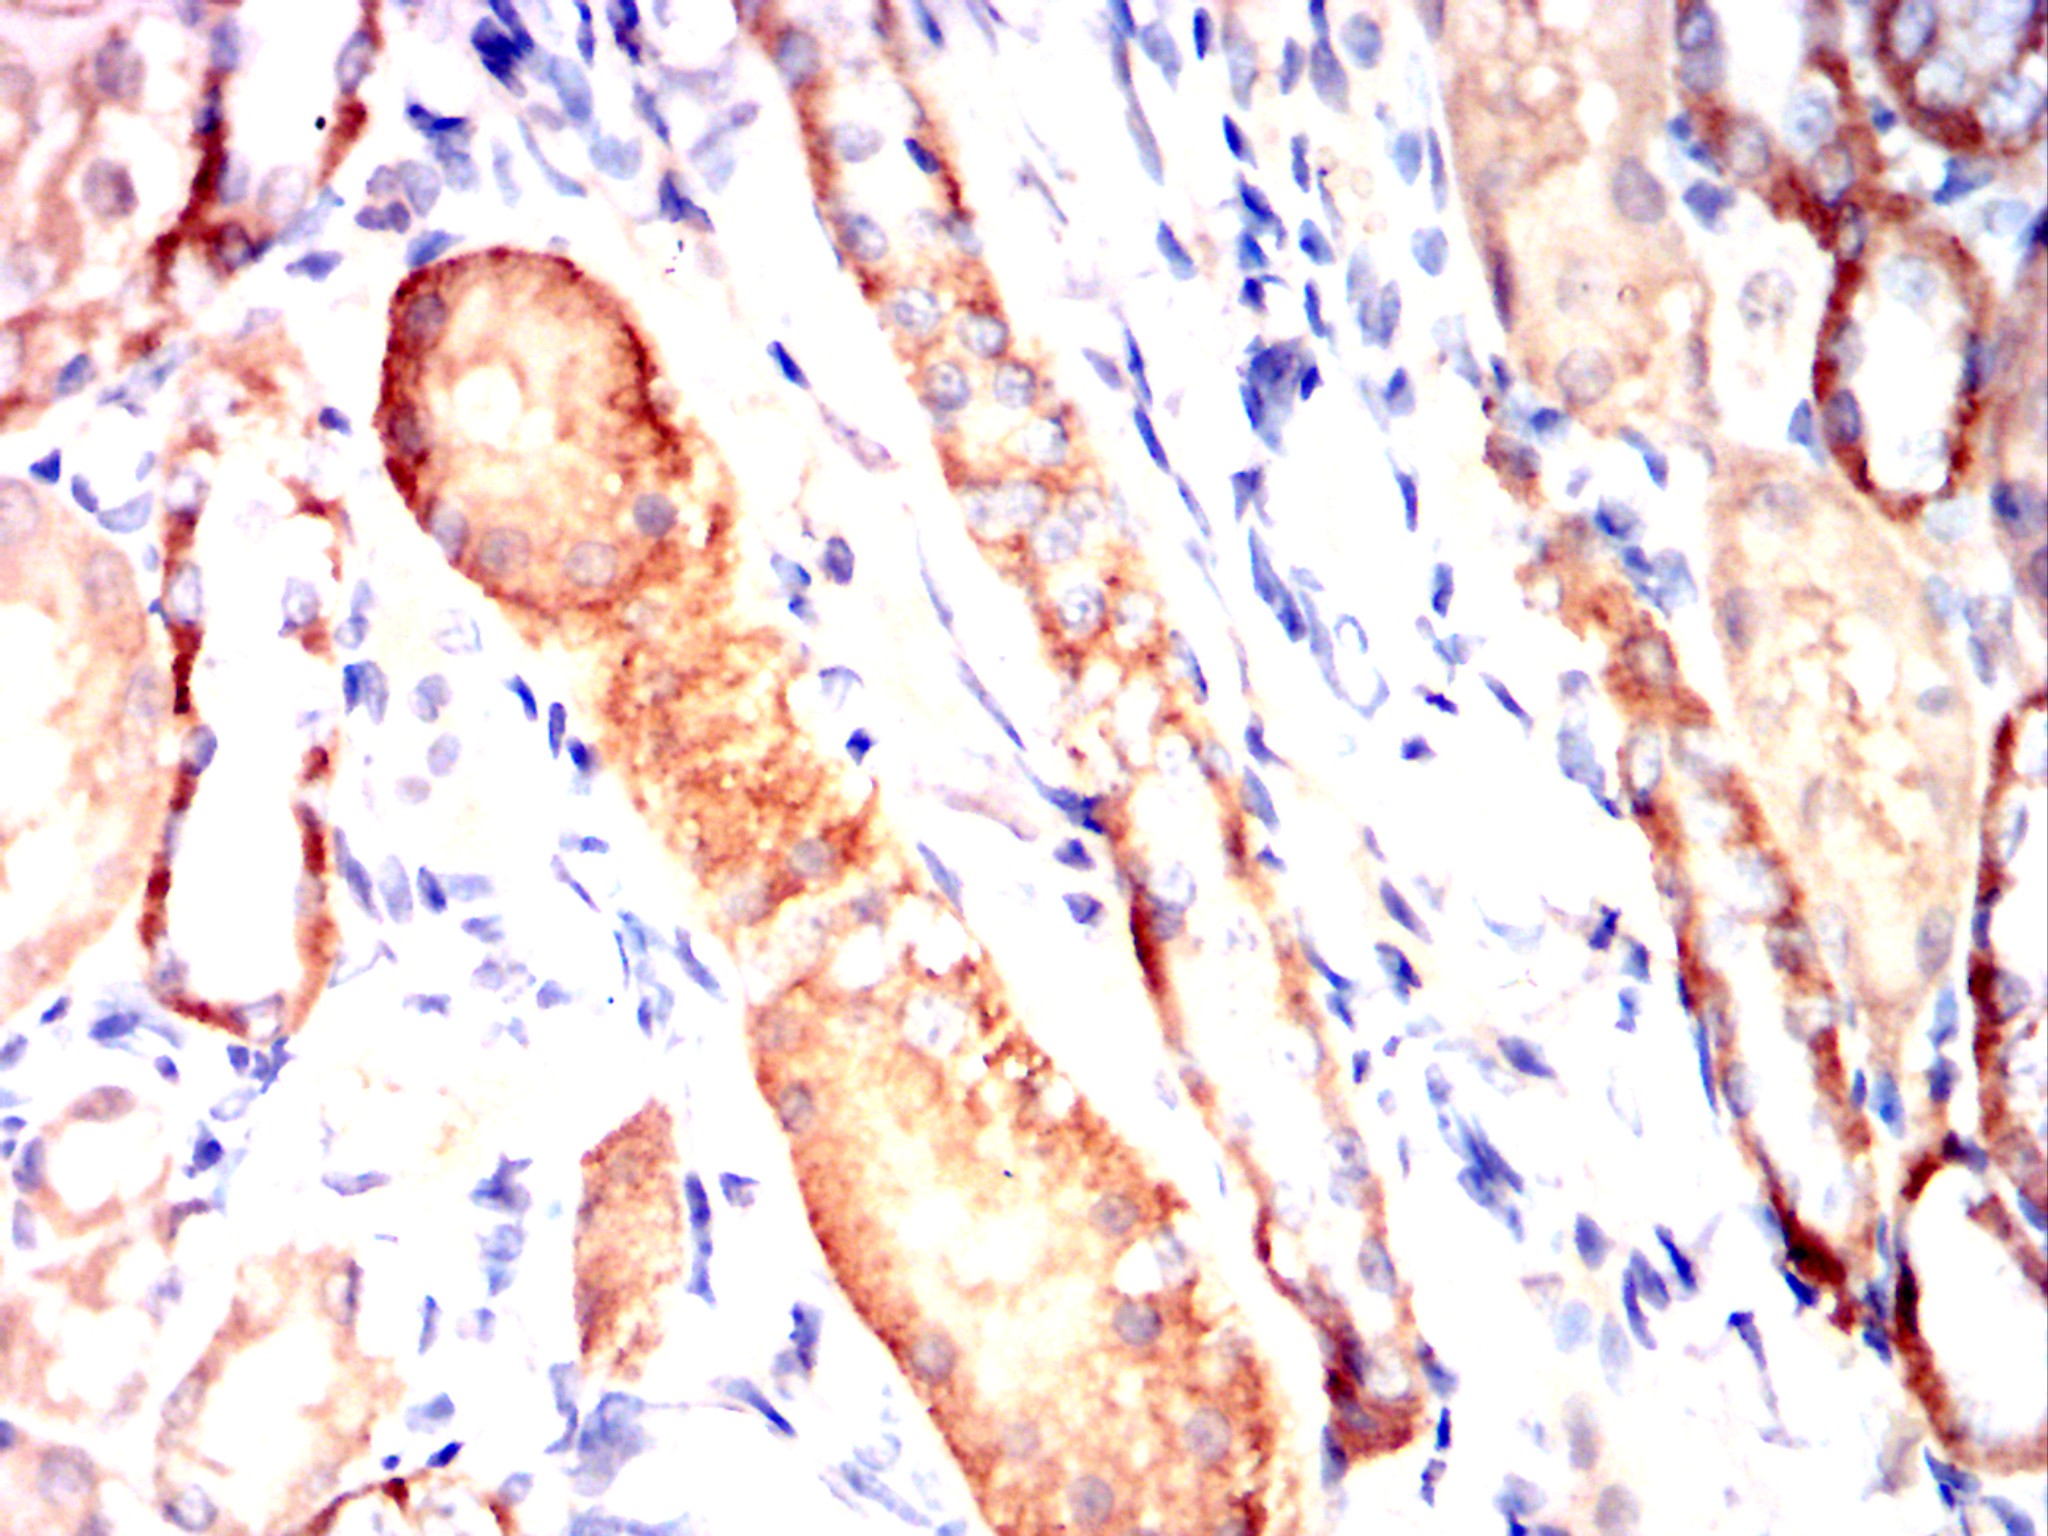

Immunohistochemical analysis of paraffin-embedded human stomach cancer tissues using CD14 mouse mAb with DAB staining.